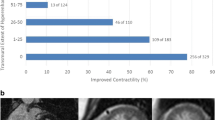

Given its established value in morphologic imaging of CAD, research efforts over the last years have focused on providing information beyond the assessment of coronary stenosis and atherosclerotic vessel wall changes. To date, CT offers two different approaches to assess the functional relevance of a given stenosis: (A) myocardial perfusion imaging (which can be performed in a dynamic or static fashion) and (B) the calculation of a CT-based fractional flow reserve (CT-FFR). CT myocardial perfusion is based on the first-pass effect of iodinated contrast media through the myocardium during vasodilator stress (pharmacologically induced using regadenoson, adenosine, or dipyridamole). The study can either be performed by obtaining one single scan during maximum enhancement (also referred to as “static” or “snapshot/single-shot” perfusion imaging) or by acquiring multiple scans during contrast passage (i.e., a “dynamic,” time-resolved imaging of myocardial perfusion). The benefit of the “snapshot” protocol is the reduction of radiation exposure, whereas the “dynamic” protocol enables the absolute quantification of myocardial blood flow and volume. Perfusion defects as obtained by these techniques are identified as areas of hypo-attenuated myocardium compared to perfusion at baseline. While reversible malperfusion indicates ischemic myocardium, persistent perfusion defects are considered to represent myocardial scar tissue [20, 21]. The calculation of the CT-FFR using flow dynamics from coronary computed tomography angiography images is another noninvasive method for the assessment of flow dynamics [22]. This novel approach allows lesion-specific flow analysis throughout the coronary tree without additional imaging or vasodilator stress, i.e., this calculation is based on the original CCTA examination. The currently most widely used technique (known as FFRCT) uses a complex reconstruction algorithm to create a three-dimensional (3D) model of the coronary arteries and assess the left ventricular mass which is directly proportional to the total blood flow at rest. By combining the information of branch diameter from the 3D model and resting blood flow, it is possible to specifically calculate the blood flow for each coronary segment (see an example in Figs. 15.2 and 15.3). Recently, freely available and simplified approaches using a one-dimensional (1D) analysis (cFFR) are under investigation [23].

Example of a CT-based derivation of fractional flow reserve model (CT-FFR, upper bar) and source coronary CT datasets demonstrating diffuse calcified and non-calcified plaques with hemodynamically relevant coronary stenosis present in the distal left anterior descending coronary artery (also A) and a large diagonal branch (red color-coding in the FFR model), whereas the right coronary artery and the left circumflex coronary artery (C and B, respectively) have diffuse coronary artery disease without hemodynamically relevant coronary lesions